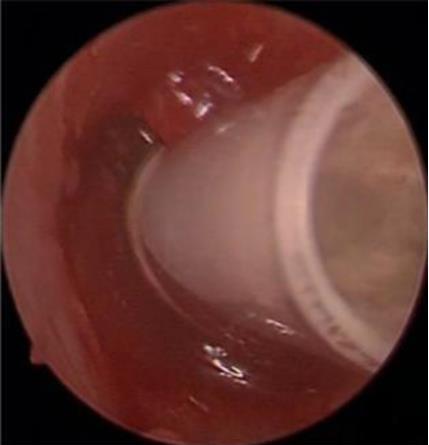

• 医用生物蛋白胶应用于耳内镜下鼓膜修补术的临床疗效

摘要:目的 分析医用生物蛋白胶应用于耳内镜下鼓膜修补术的临床疗效。方法 回顾性分析2022年10月-2023年10月该院收治的60例单纯鼓膜穿孔患者的临床资料,根据手术方法不同,将患者分为研究组和对照组,各30例。研究组术中使用医用生物蛋白胶粘合残余鼓膜和修补材料;对照组术中采用明胶海绵覆盖修补鼓膜。观察两组患者术后的鼓膜愈合情况(鼓膜愈合率、愈合时间、干耳时间和外耳道上下径)和并发症发生情况;于手术前后,采用纯音测听法(500、1 000、2 000、4 000 Hz),测量两组患者气导阈值,观察听力改善程度;采用视觉模拟评分法(VAS)评分,评估患者术后疼痛程度。结果 两组患者术后鼓膜愈合率、愈合时间、外耳道上下径和并发症发生率比较,差异均无统计学意义(P > 0.05)。研究组术后平均气导听阈明显低于对照组,差异有统计学意义(P < 0.05)。研究组术后干耳时间短于对照组,术后第1天疼痛VAS评分明显低于对照组,差异均有统计学意义(P < 0.05)。结论 医用生物蛋白胶应用于耳内镜下鼓膜修补术,可有效地降低气导听阈,缩短干耳时间,减轻患者疼痛,且不增加并发症发生率,值得临床推广应用。